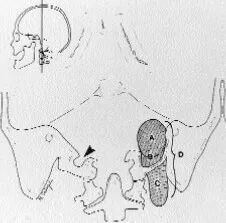

磨除枕骨颈静脉突(Jugular process),贯通颈静脉孔与颈部;暴露颈静脉孔,但无需暴露颈静脉孔上方的半规管及外侧的乳突段面神经,“没有暴露,就没有伤害”。

颈静脉孔区位置深在,结构繁多,名称繁杂,方寸之间,颈内动脉、椎动脉、颈内静脉、颈静脉球、横窦、乙状窦、髁后导静脉、枕骨髁、颈静脉结节、颈静脉突、骨迷路、寰椎横突、二腹肌、头外侧直肌、枕下三角、耳大神经、面神经、舌咽、迷走、副及舌下神经等结构密集,空间关系复杂